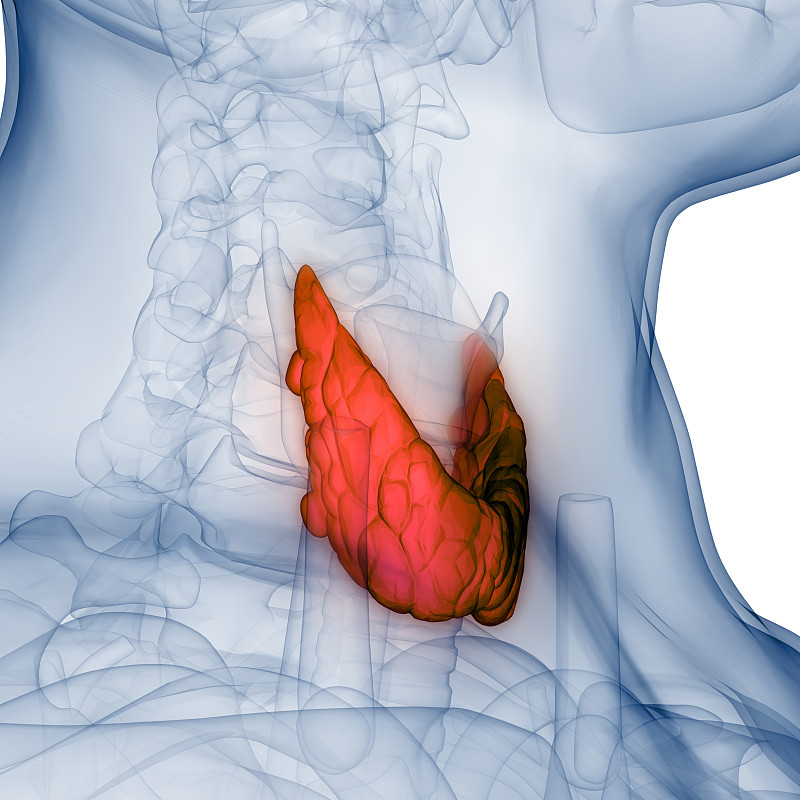

人体内分泌系统图解详情

JPG